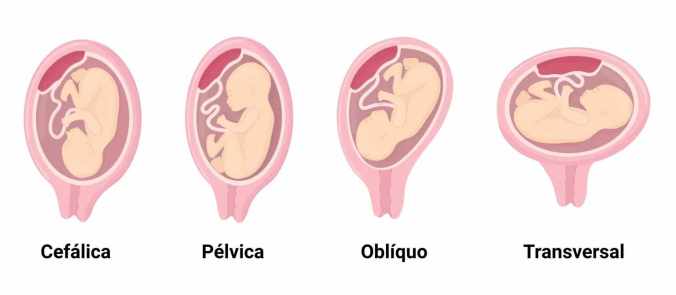

Quando falamos em apresentação pélvica, estamos nos referindo à maneira como o bebê se encaixa no útero, especificamente em relação ao colo do útero. Em vez da posição mais comum, que é a cefálica (com a cabeça para baixo), o bebê pélvico está com os pés ou as nádegas voltadas para a saída. Essa é a grande diferença, e é ela que gera a maioria das preocupações.

Existem diferentes tipos de apresentação pélvica, viu? Tem a pélvica completa, onde o bebê está ‘sentadinho’ com as pernas cruzadas; a pélvica incompleta ou franca, que é a mais comum, com as pernas esticadas e os pés perto da cabeça; e, mais raramente, a apresentação podálica, onde um ou os dois pés estão para baixo. Cada tipo tem suas particularidades e influencia nas decisões médicas.

Se o bebê não virar, qual a melhor opção de parto? Essa é uma decisão que precisa ser muito bem discutida com sua equipe médica. Historicamente, o parto pélvico vaginal era mais comum, mas hoje, a cesariana é a via de parto mais segura e recomendada para a maioria dos casos de apresentação pélvica, especialmente em primigestas (primeira gravidez).

Em situações muito específicas, com critérios rigorosos (como tipo de pélvica, tamanho do bebê, experiência da equipe e desejo da mãe), o parto vaginal pode ser considerado. No entanto, é vital que a mãe esteja ciente dos parto pélvico riscos e que o hospital tenha toda a estrutura e equipe preparada para qualquer intercorrência. A segurança da mãe e do bebê vem sempre em primeiro lugar.